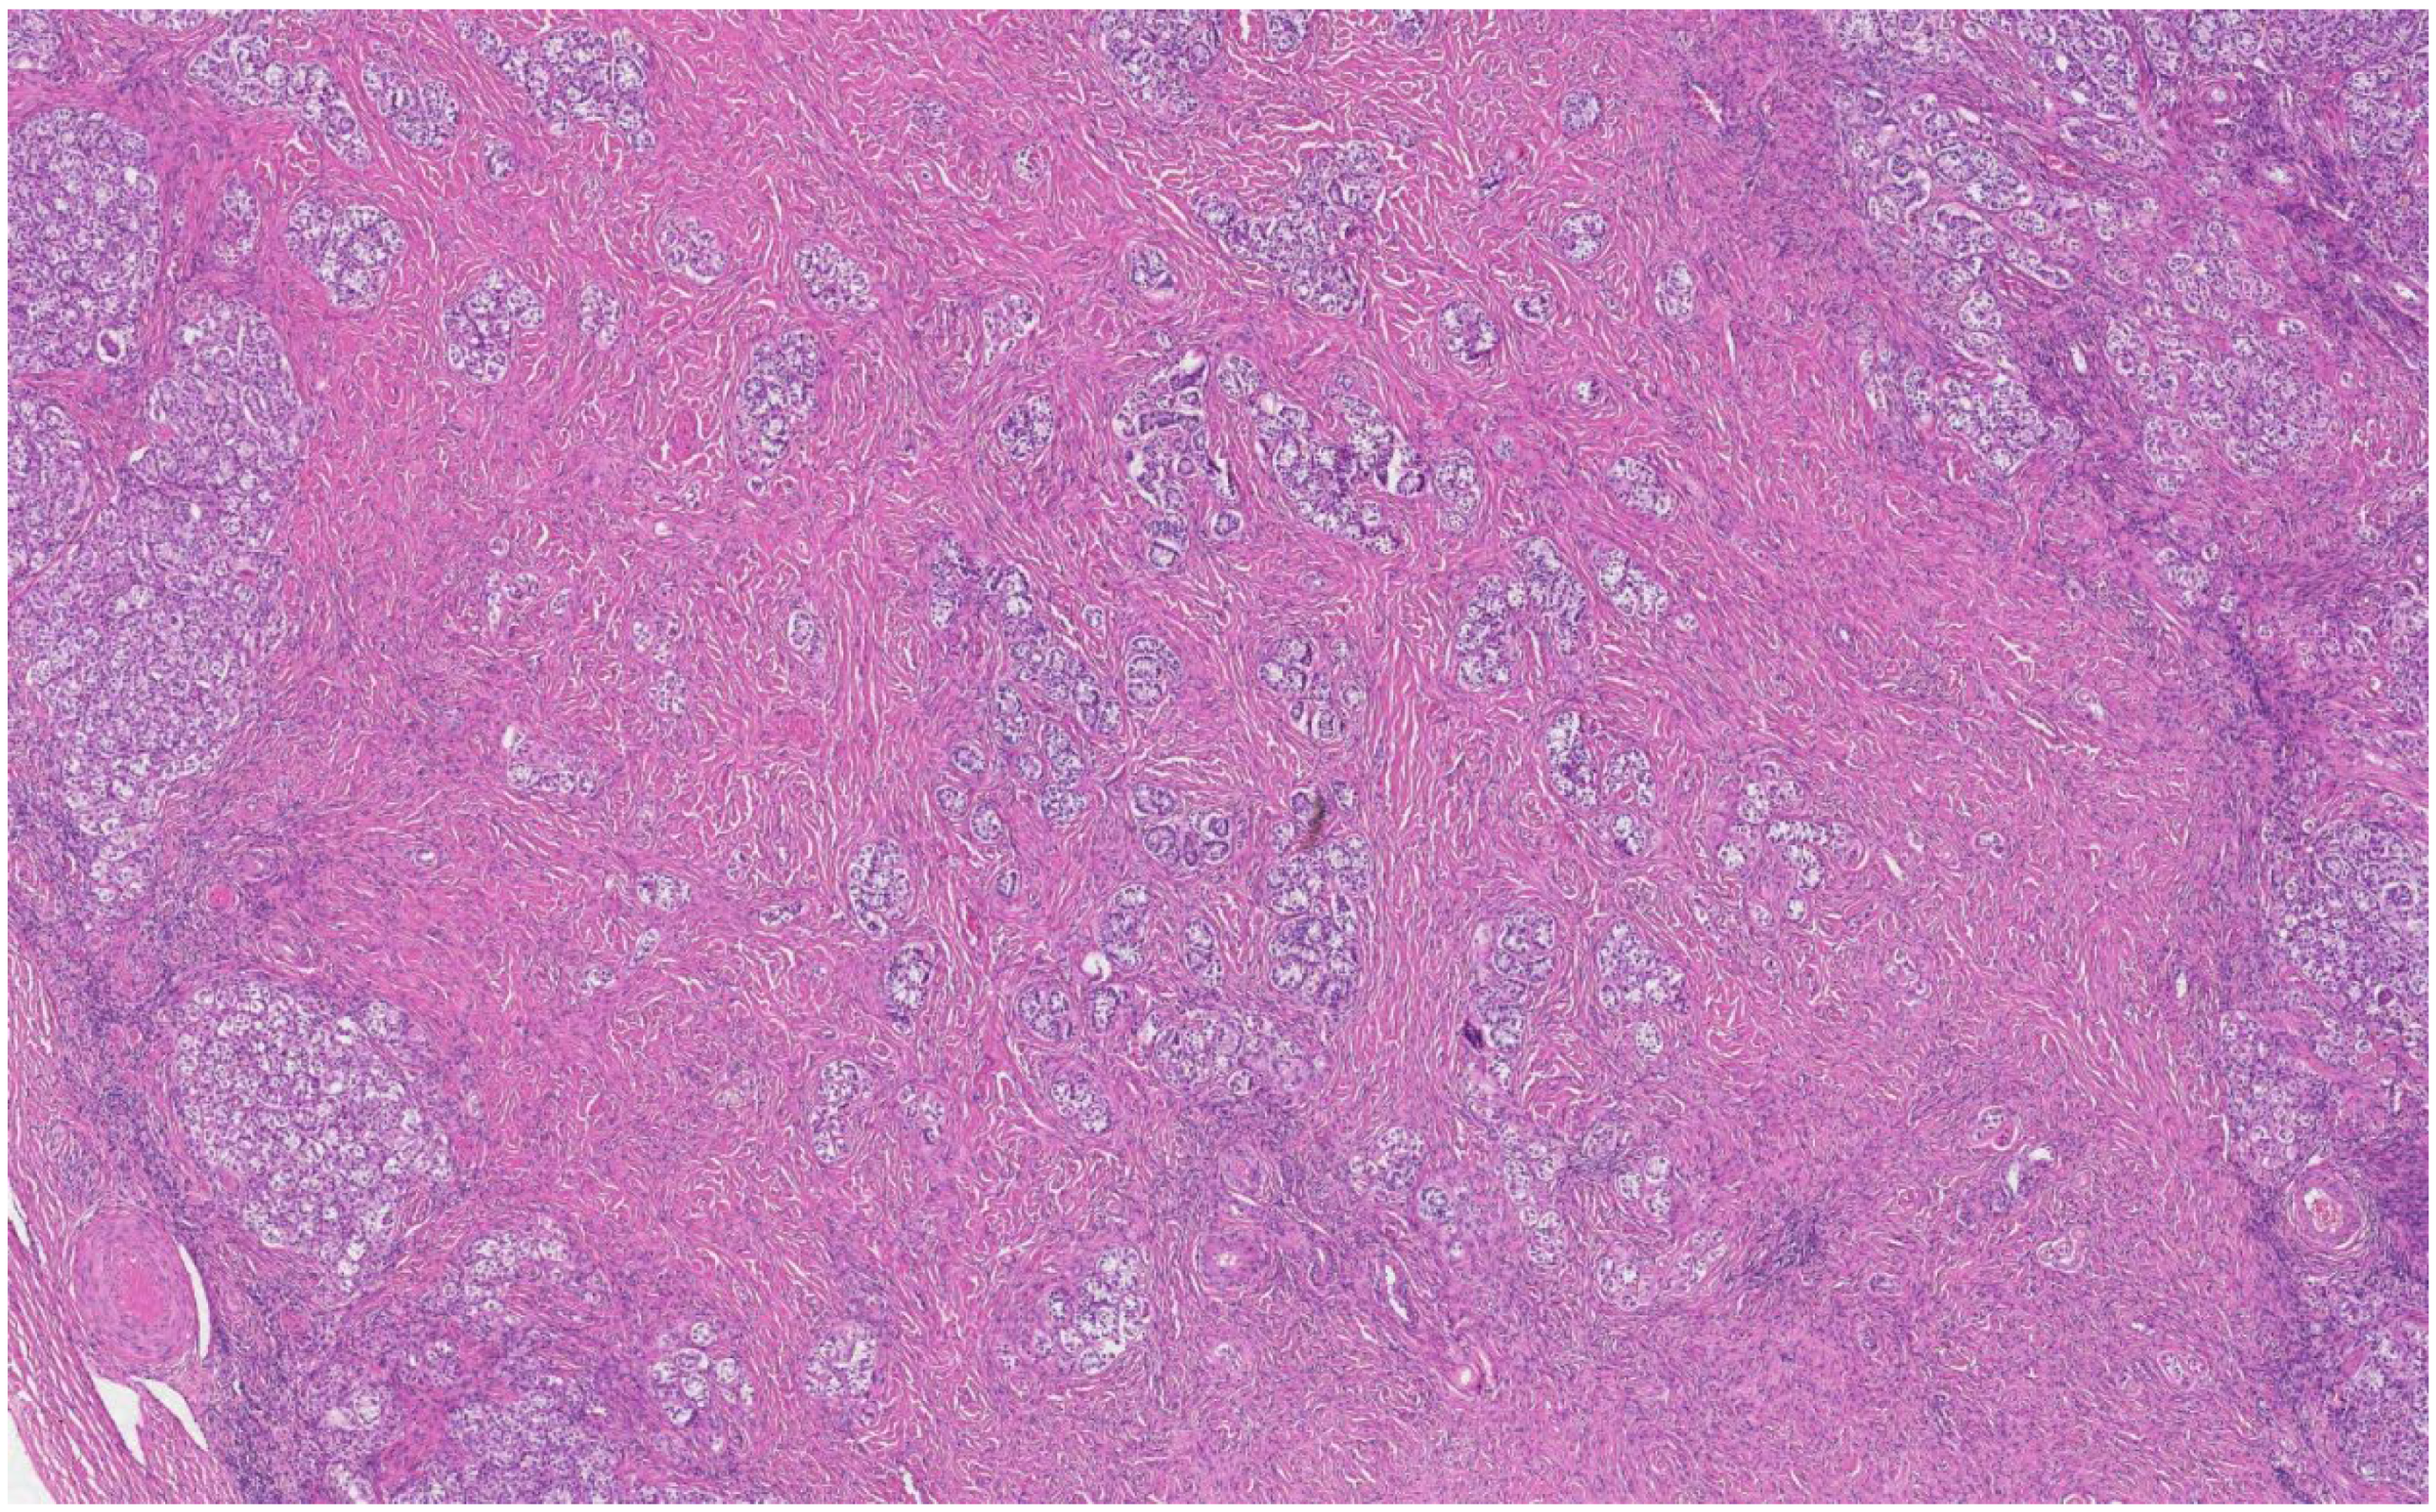

The histological analysis of the patient’s removed gonads revealed that there were hypoplastic testicles, which is a clinical sign of androgen insensitivity syndrome (Figure 3, Figure 4, Figure 5 and Figure 6). After the operation, testosterone analysis was repeated-hormone level significantly decreased to 0.83 nmol/L, which is a normal female-range value for a woman at that age.

Figure 5. Small tubules composed of immature Sertoli cells separated by Leydig cells (arrow) and nodular Leydig cell hyperplasia (arrowhead) (H&E staining, ×50).